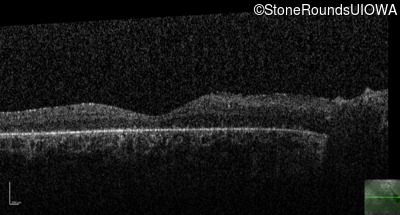

Visit at age: 28 years

Optical Coherence Tomography - Right - Hand Motion

Exemplar / OCT Stack

OCT Stack